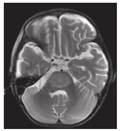

共2例,1例表现为半卵圆中心、脑室周围白质T2WI高信号,1例表现为双侧顶枕叶为主T2WI高信号,复查好转。

化疗药物,尤其是甲氨蝶呤等,可能会导致脑白质毒性改变[13]。这种白质毒性作用可有或无临床症状,呈一过性或永久性。本组1例患儿化疗前头颅MRI表现正常,接受化疗后6个月出现肢体乏力,言语不清,步态异常,MRI检查半卵圆中心及脑室周围白质T2WI呈高信号。放射治疗诱导的肿瘤,尤其是脑肿瘤,是儿童白血病患者最常见的二次肿瘤,胶质瘤最常见,其次是室管膜瘤、淋巴瘤、脑膜瘤[14]。5岁或5岁以内接受过颅脑放疗,或有基因易感性(如双侧视网膜母细胞瘤,神经纤维瘤病Ⅰ型),或骨髓移植后的儿童风险明显增大,且治疗诱导的肿瘤更具侵袭性[15]。颅脑放疗和肿瘤发生之间的潜伏期长短变化较大,本组1例为脑干胶质瘤,发生于白血病起病后3年余,无放疗史,可能与潜在遗传因素有关。